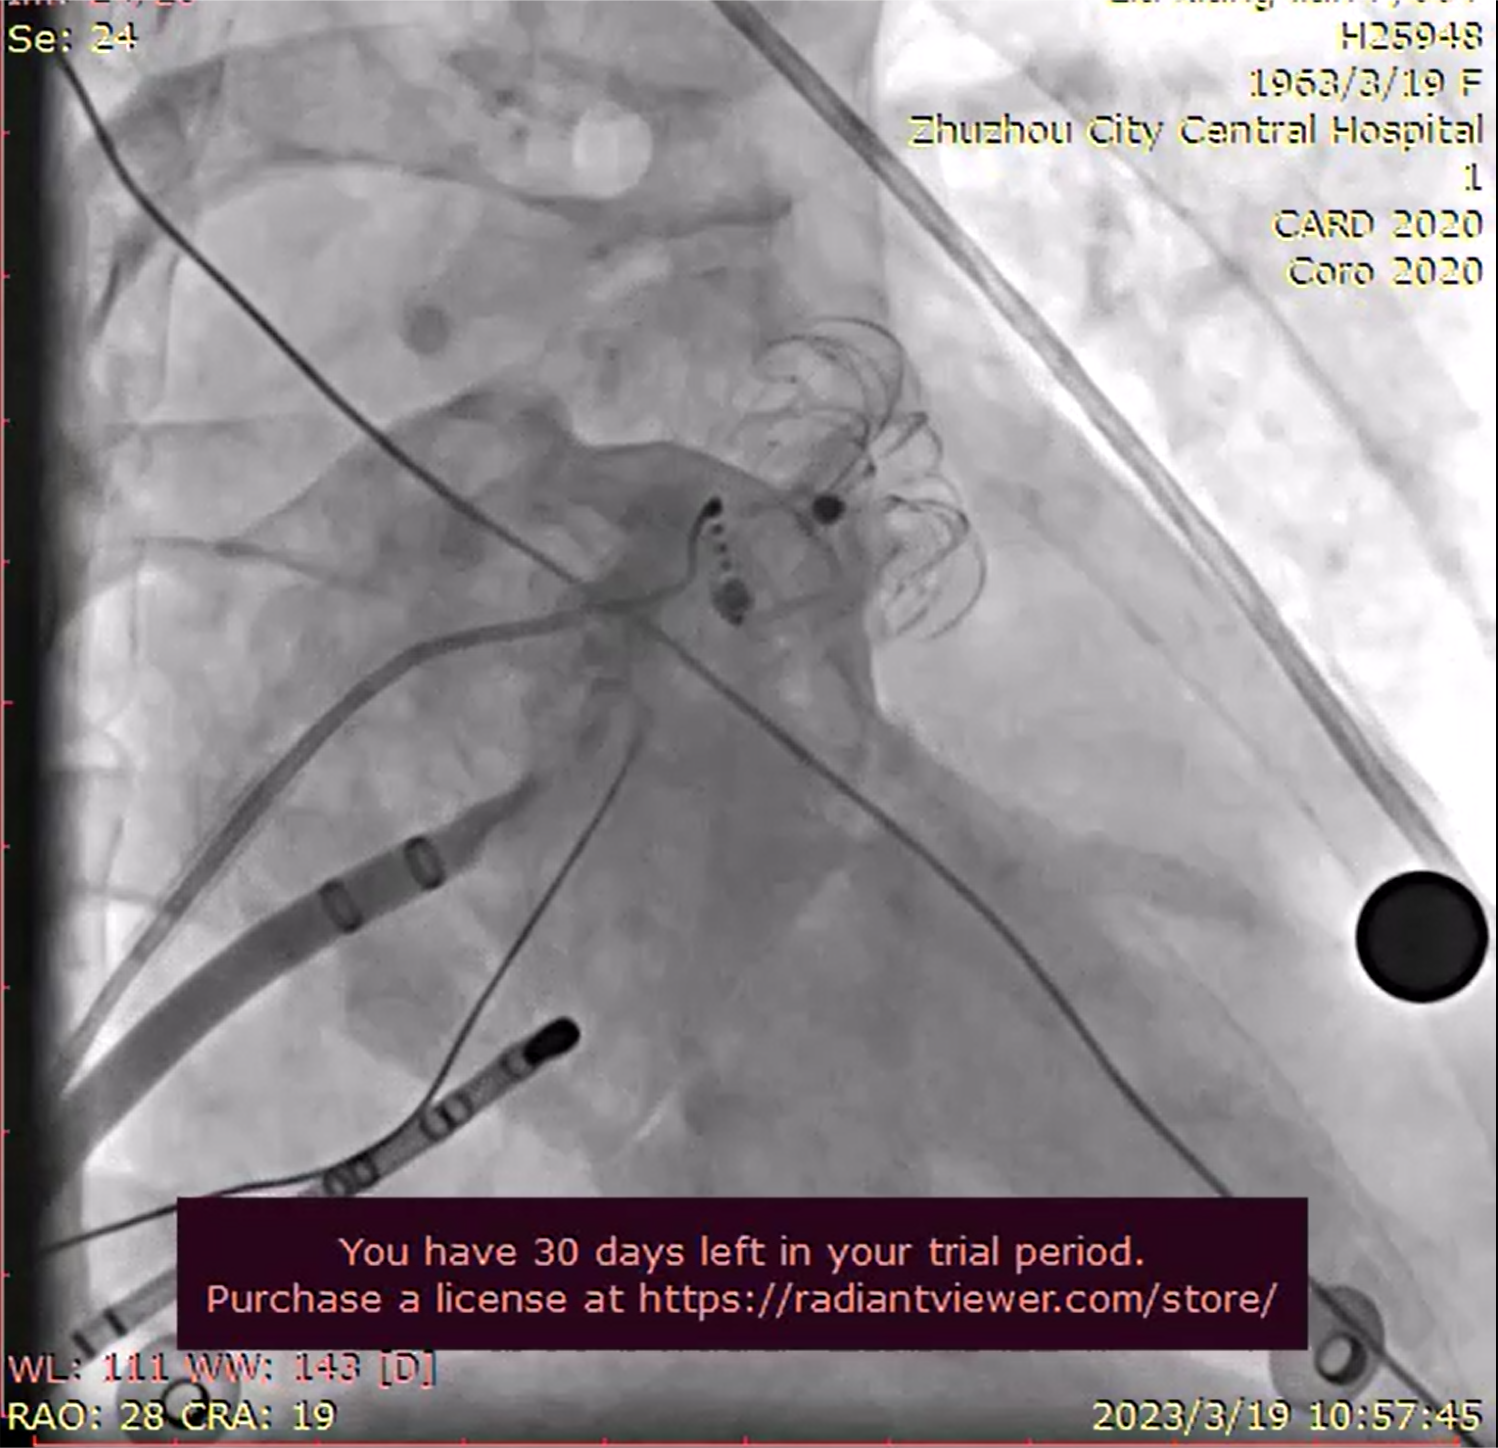

2023年3月19日,由株洲市中心医院主办、广东脉搏医疗有限公司协办的《“双盘内塞”式Leftear®左心耳封堵器系统全国巡讲—株洲站》学术交流活动在株洲市中心医院成功举办。此次活动以学术会议加手术的方式开展,会议同时邀请到了上海市第十人民医院徐亚伟教授和上海市第四人民医院陈维教授现场学术授课和手术交流。学术活动期间共开展了4台左心耳封堵手术全部圆满成功,其中包括2台一站式手术,植入的Leftear®左心耳封堵器型号分别为:2台Leftear®常规型号,2台“小伞大盘”特殊型号。

手术过程

四例手术中的第三例和第四例采用了“小伞大盘”的特殊型号:第三例左心耳造影后,经专家评估,该患者左心耳结构为菜花型,且心耳深度较浅,使用传统内塞式左心耳封堵器手术难度大,经专家评估讨论,最终选用MB02-2537“小伞大盘”的特殊型号,手术过程中一次性植入成功;第四例为三年前拟采用某进口内塞式左心耳封堵器后无法选型植入的患者,经左心耳造影后发现,该病人左心耳形状为仙人掌型,开口较大且着陆区狭长,专家研究探讨后,决定选用MB02-2133型号,手术中一次性封堵成功。

术后,徐亚伟教授、陈维教授、欧阳繁教授与众专家医生一起交流总结时,欧阳繁教授表示:今天的四例手术,两台一站式,2台采用了特殊型号,实战说明了Leftear®左心耳封堵器系统是一款优秀的左心耳封堵器系统产品,无论是一站式还是单封堵都表现出了优秀的临床有效性、安全性和易用性,同时,对于左心耳结构复杂的患者,Leftear®有10个常规型号加6个特殊型号,可以应对临床手术过程中各种突发的复杂情况。